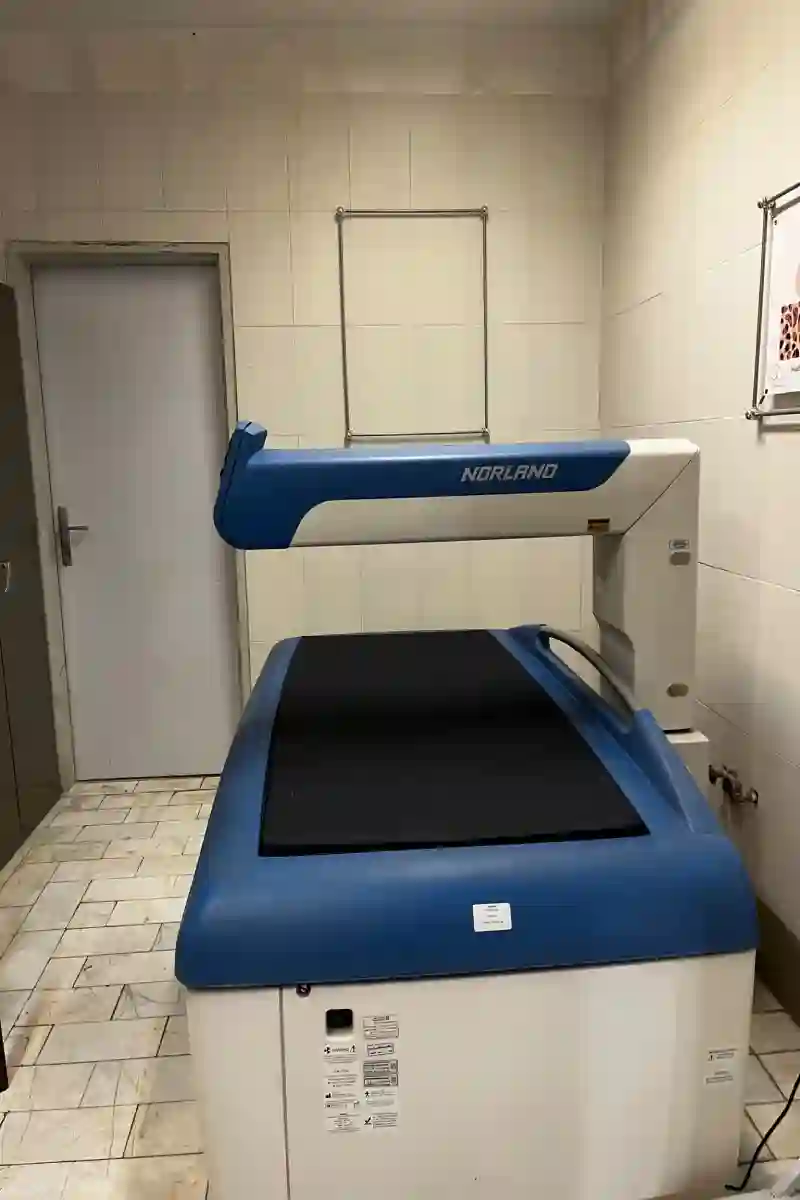

اين مركز راديولوژي و سونوگرافي مجهز به بهترين و حرفه اي ترين تجهيزات تصويربرداري پزشكي بوده و با كادر مجرب و حرفه اي خود زير نظارت مستقيم پزشك حاذق متخصص راديولوژي آماده ارائه خدمت به تمامي بيماران عزيز در زمينه تشخيص تمامي بيماري ها و مراقبتهاي دوران بارداري شامل تمامي غربالگري هاي جنين ميباشد.